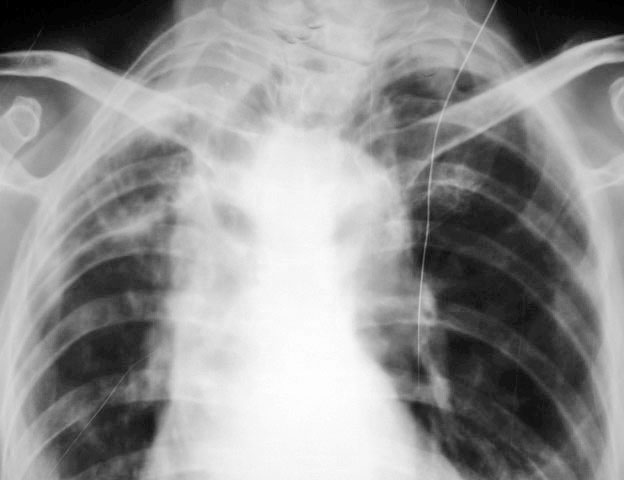

以下是引用拾荒者在2010-3-16 20:35:00的发言:[br]体位不正,肩胛骨没闪出肺野,拍照条件也不好,应该重照,否则诊断有可能与事实差距太大。

以下是引用小小医在2010-3-16 19:45:00的发言:[br]气管牵拉右移,胸段脊柱右弯畸形,慢性支气管炎,双侧胸膜增厚,左下肺炎,左下胸膜腔少量积液,建议ct

以下是引用随光逐影在2010-3-17 7:43:00的发言:[br]1)右上肺继发性肺结核。2)慢性支气管炎并左下肺感染,肺气肿。3)双侧胸膜增厚,左侧少量胸腔积液。